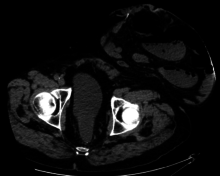

Parastomal hernia is the most common late complication of stomata through the abdominal wall, occurring in 10 to 25% of the patients.[1]

One well-known form of an artificial stoma is a colostomy, which is a surgically created opening in the large intestine that allows the removal of feces out of the body, bypassing the rectum, to drain into a pouch or other collection device.

This surgical procedure is invoked usually as a result of and solution to disease in the GIT. The procedure involves bisecting this tube, usually between the later stage of the small intestine (ileum) and the large intestine or colon, hence colostomy, and exiting it from the body in the abdominal region.

The point of exiting is what is known as the stoma. For greatest success and to minimize negative effects, it is preferable to perform this procedure as low down in the tract as possible, as this allows the maximal amount of natural digestion to occur before eliminating fecal matter from the body. The stoma is usually covered with a removable pouching system (adhesive or mechanical) that collects and contains the output for later disposal. Modern pouching systems enable most individuals to resume normal activities and lifestyles after surgery, often with no outward physical evidence of the stoma or its pouching system.